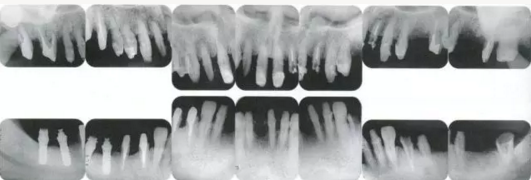

3333.png

▲圖19-12

同時(shí)期的X光片。

33333.png

▲圖19-13

佩戴最終修復(fù)體時(shí)的正面照片。